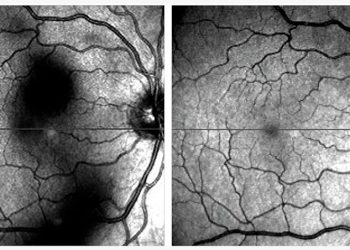

Regresión espontánea de una masa subretiniana periférica: a propósito de un caso de PEHCR